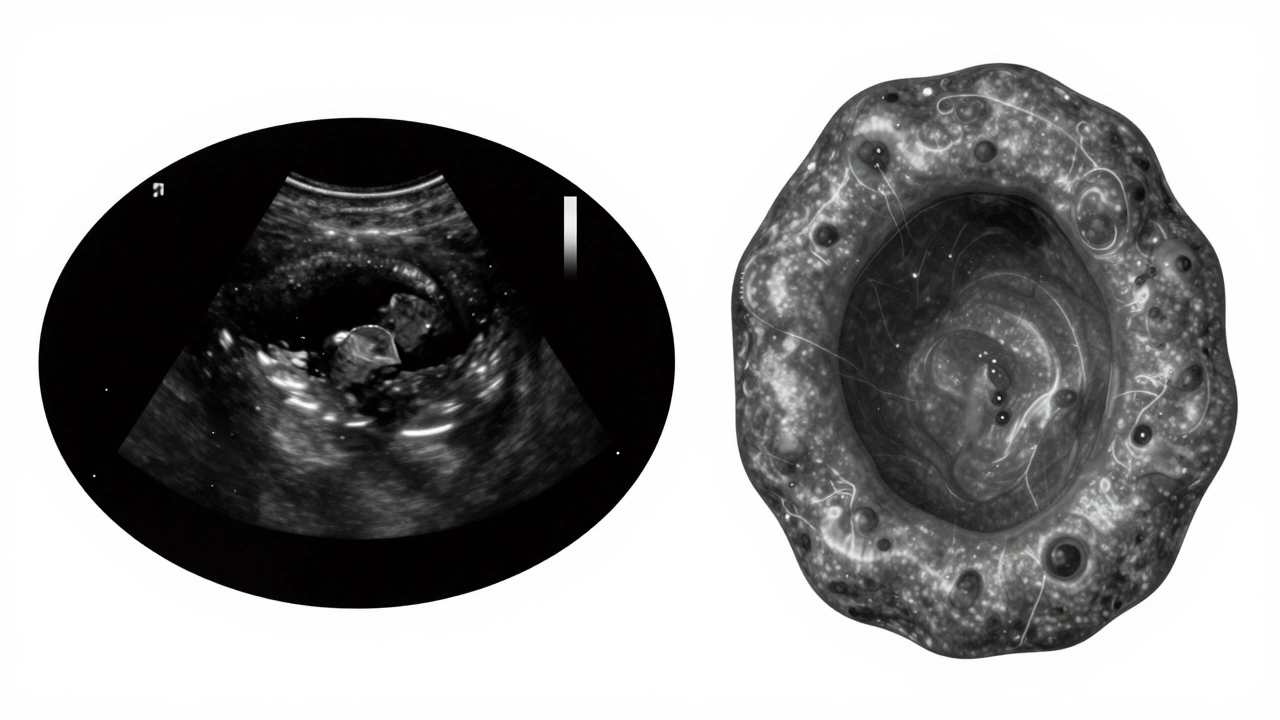

Как отличить кисту от опухоли?

Это главный вопрос, который волнует всех, кто видит результаты УЗИ. Вот как различаются киста и опухоль по картинке:

Сравнение кисты и опухоли на УЗИ

Признак Киста Опухоль

Эхогенность Анэхогенная (черная) Гиперэхогенная или изоэхогенная (серая)

Стенки Тонкие, ровные Толстые, неровные, бугристые

Внутренняя структура Однородная, без включений Неоднородная, с участками плотной ткани

Кровоток Отсутствует Присутствует внутри и вокруг

Задний эхо-усиление Есть Отсутствует

Если на УЗИ видна опухоль - это не значит рак. Это просто твердое образование. Оно может быть доброкачественным, например, фиброаденомой в молочной железе или гемангиомой в печени. Но его нужно исследовать глубже: с помощью МРТ, биопсии или динамического наблюдения.

Сравнение кисты и опухоли на УЗИ: чёрная жидкостная структура против неровного серого образования с кровотоком.